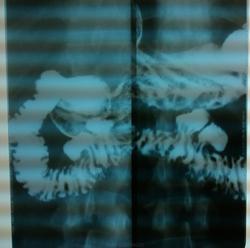

Пациентка, 47 лет. Жалобы на боли в эпигастрии и правом подреберье после еды.

Красивая картина.Так дружно, рядышком

Такие большие дивертикулы могут же вызывать сильные боли?

Судить о дивертикулите затрудняюсь. Недавно Андрей Юрьевич напоминал признаки дивертикулита ".....Рентгенологическими симптомами дивертикулита является нечеткость и неровность контура дивертикула, длительная задержка в нем бариевой взвеси, наличие слизи; в полости больших дивертикулов иногда отечные складки создают картину дефектов наполнения. Кишка раздражена, очень быстро освобождается от бариевой взвеси, просвет кишки часто спастически сокращен, рельеф слизистой оболочки представлен широкими складками. ...."http://www.radiomed.ru/cases/tolstaya-kishka. Они универсальны. Вы видели при проведении обследования что - нибудь из перечисленного?

Когда я увидела, там уже был контраст, с задержкой на всём протяжении исследования.

Задержка опорожения - один из перечисленных признаков

основной признак дивертикулита - наличие остаточного бария в дивертикулах после опорожнения на протяжении всего исследования.